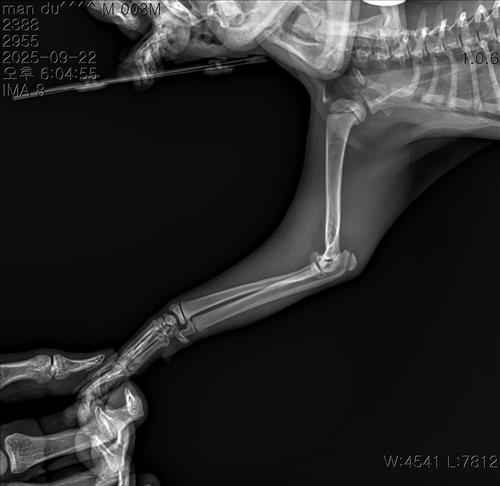

만지면 아파하길래 냅다 병원가서 엑스레이 진단을 받았어요

왼쪽 앞다리 팔꿈치 부분 성장판 골절이라고 진단을 받고 수술을 권장 받았어요..

아직 어린 우리 아이에게 이런 일이 생겨서 많이 놀라셨을 것 같아요. 말씀주신 상황과 사진을 보면 상완골 원위단, 성장판 골절이 확인됩니다.

깁스 치료는 전위가 거의 없는 "안정적" 골절에서는 가능하지만, 우리 아이의 경우 주관절의 불안정성으로 파행이 생길 수 있어 깁스만으로는 예후가 좋지 않을 듯 합니다. 깁스로 버틴다 해도 비뚤게 붙거나, 성장판 손상으로 앞다리 변형이 남을 수 있습니다.

따라서, 정확히 맞추고 고정하는 수술치료가 가장 좋은 치료 방법입니다. 나이가 어려 회복이 빠르고, 정상 보행 가능성이 높으니 수술치료를 고려해보시는 것을 권해드립니다.